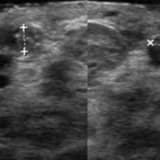

Doğumsal omurga ya da omurilik hastalıkları genelde çok kolay tanınırlar çünkü gözle görülür bulgular ortaya çıkartmaktadırlar. Ancak bu hastalık grubunda olan tethered cord (gergin omurilik) ilkokul çağına kadar hiçbir bulgu vermeyebilir. Yapılan bir çalışmada ilkokul çağında gece idrar kaçırma sorunu olan çocukların bir kısmında gergin omurilik sendromu olduğu tespit edilmiştir. Bu hastalıkta tanının gecikmesi sinirlerin ölmesine ve cerrahi müdahale yapılsa dahi sorunların geçmemesine neden olmaktadır. Gergin omurilik hastalığı yeni doğan döneminde 1-2 dakika sürecek bir ultrasonografi incelemesiyle kesin olarak tanınabilmektedir. Radyoloji uzmanınca yapılacak bir spinal-sakral ultrasonografi incelemesi yeterli olacaktır.